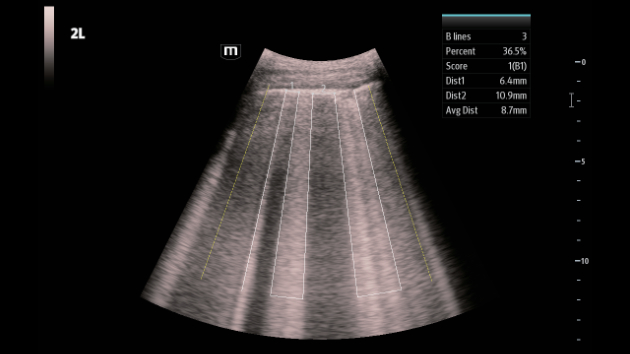

Soluzioni di diagnostica per immagini complete con tecnologia ZST+

La piattaforma ZST+ è un'innovazione straordinaria, che rappresenta un'evoluzione nel campo dell'ecografia. Grazie alla trasformazione delle metriche a ultrasuoni dal beamforming convenzionale all'elaborazione basata sui dati di canale, supera la tradizionale limitazione del trade-off tra risoluzione spaziale, risoluzione temporale e uniformità dei tessuti, offrendo una qualità d'immagine eccezionale per infinite soluzioni di imaging con miglioramenti continui.